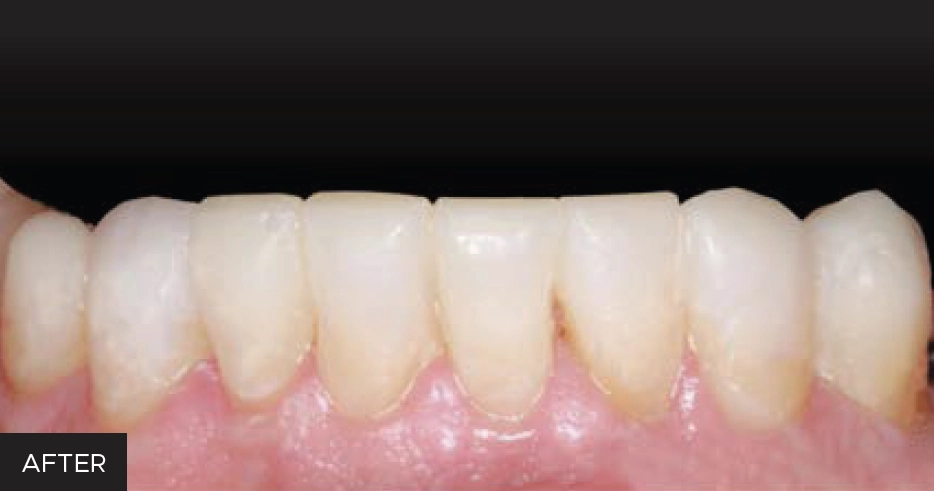

Having the capability to quickly and predictably transfer a mock-up into a patient’s mouth using composite resin allows clinicians to offer their patients alternative treatment options. This procedure provides an effective way to restore multiple teeth in the arch as temporary, transitional and/or permanent restorations. (FIG. 1)

Before photo of a worn/broken lower dentition (#’s 21-27) before using the injection molding technique.